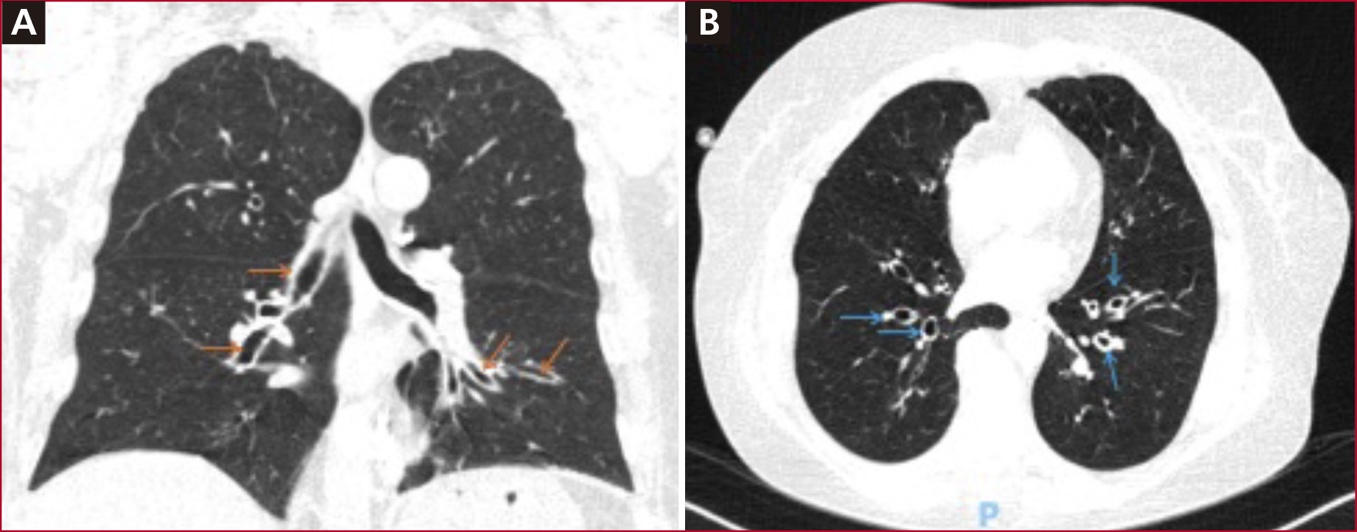

Ante el deterioro clínico, se consideró realizar una tomografía computarizada de tórax que reveló bronquiectasias cilíndricas y engrosamiento de paredes bronquiales especialmente en el hilio, que son típicas en los pacientes con infección por metaneumovirus (Figura).

Figura. Tomografía de tórax. A. Pequeñas bronquiectasias cilíndricas en el aspecto medial de ambos lóbulos inferiores (flechas naranjas) especialmente en el pulmón izquierdo. B. Ligero engrosamiento de las paredes bronquiales (flechas azules).